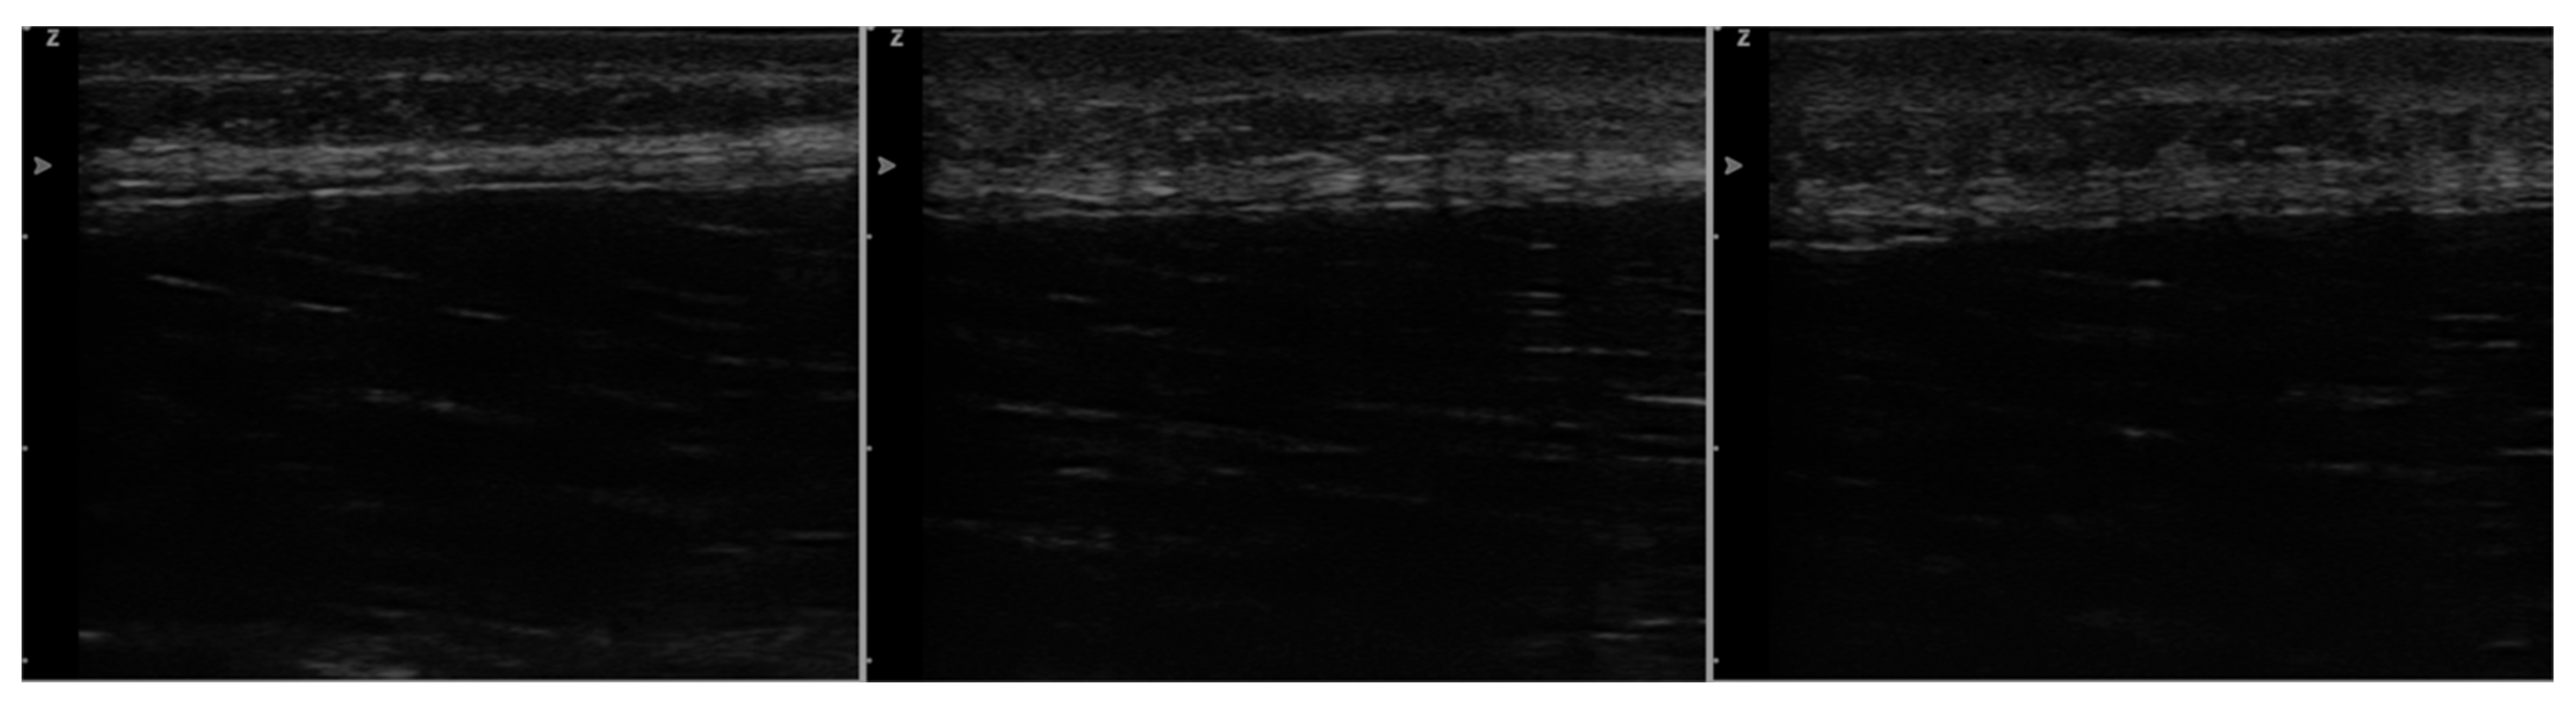

2.3.1. Ultrasound Imaging

3.4. Superficial Fascia Changes